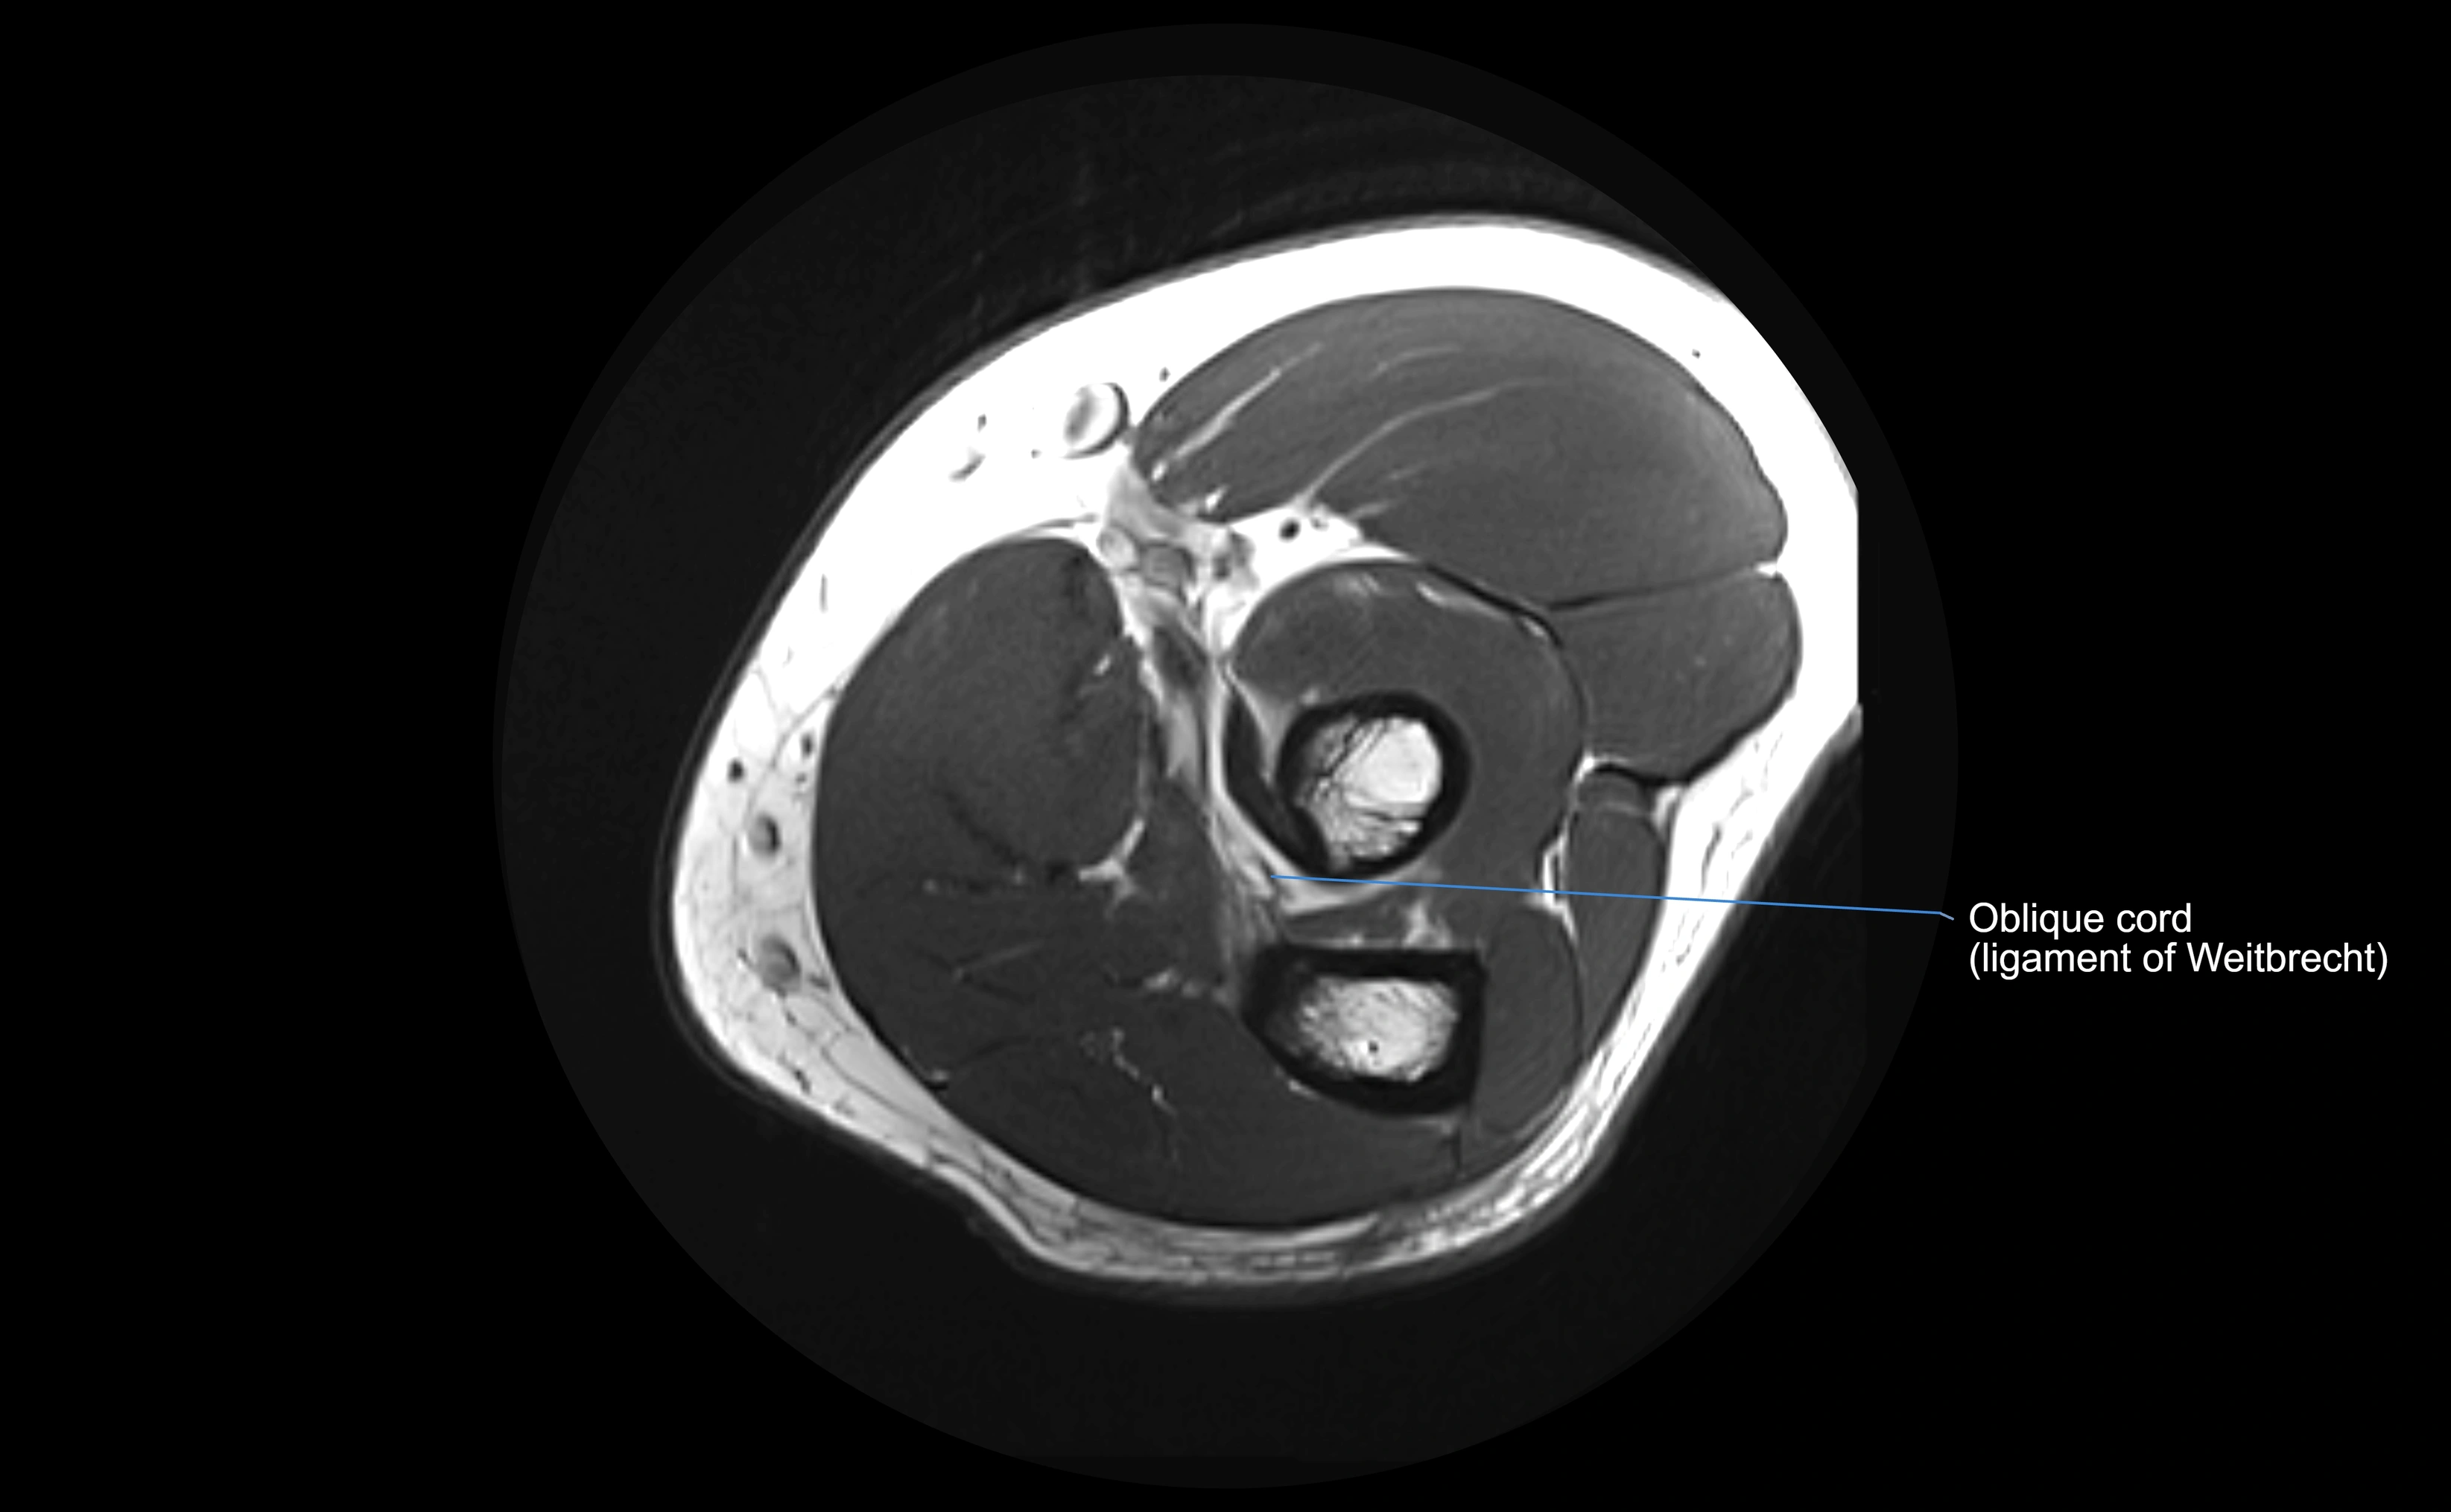

MRI Appearance

T1-weighted images:

• Ligament: low signal intensity (dark), appearing as a continuous band around the radial head.

• Adjacent fat and marrow: bright, creating contrast with the ligament.

• Thickening or disruption indicates injury or fibrosis.

• Joint capsule and synovium seen as thin low-signal lines contiguous with ligament margins.

T2-weighted images:

• Ligament: low signal (dark) with clear delineation from joint fluid.

• Fluid or edema: bright hyperintense, separating or surrounding the ligament in partial tears.

• Complete tear: discontinuity or non-visualization of ligament fibers, often with joint effusion.

Proton Density Fat-Saturated (PD FS):

• Normal: dark, well-defined band outlining the radial head.

• Partial tear: irregular or bright hyperintense signal within or adjacent to ligament fibers.

• Joint effusion and reactive synovitis appear bright and are well visualized.